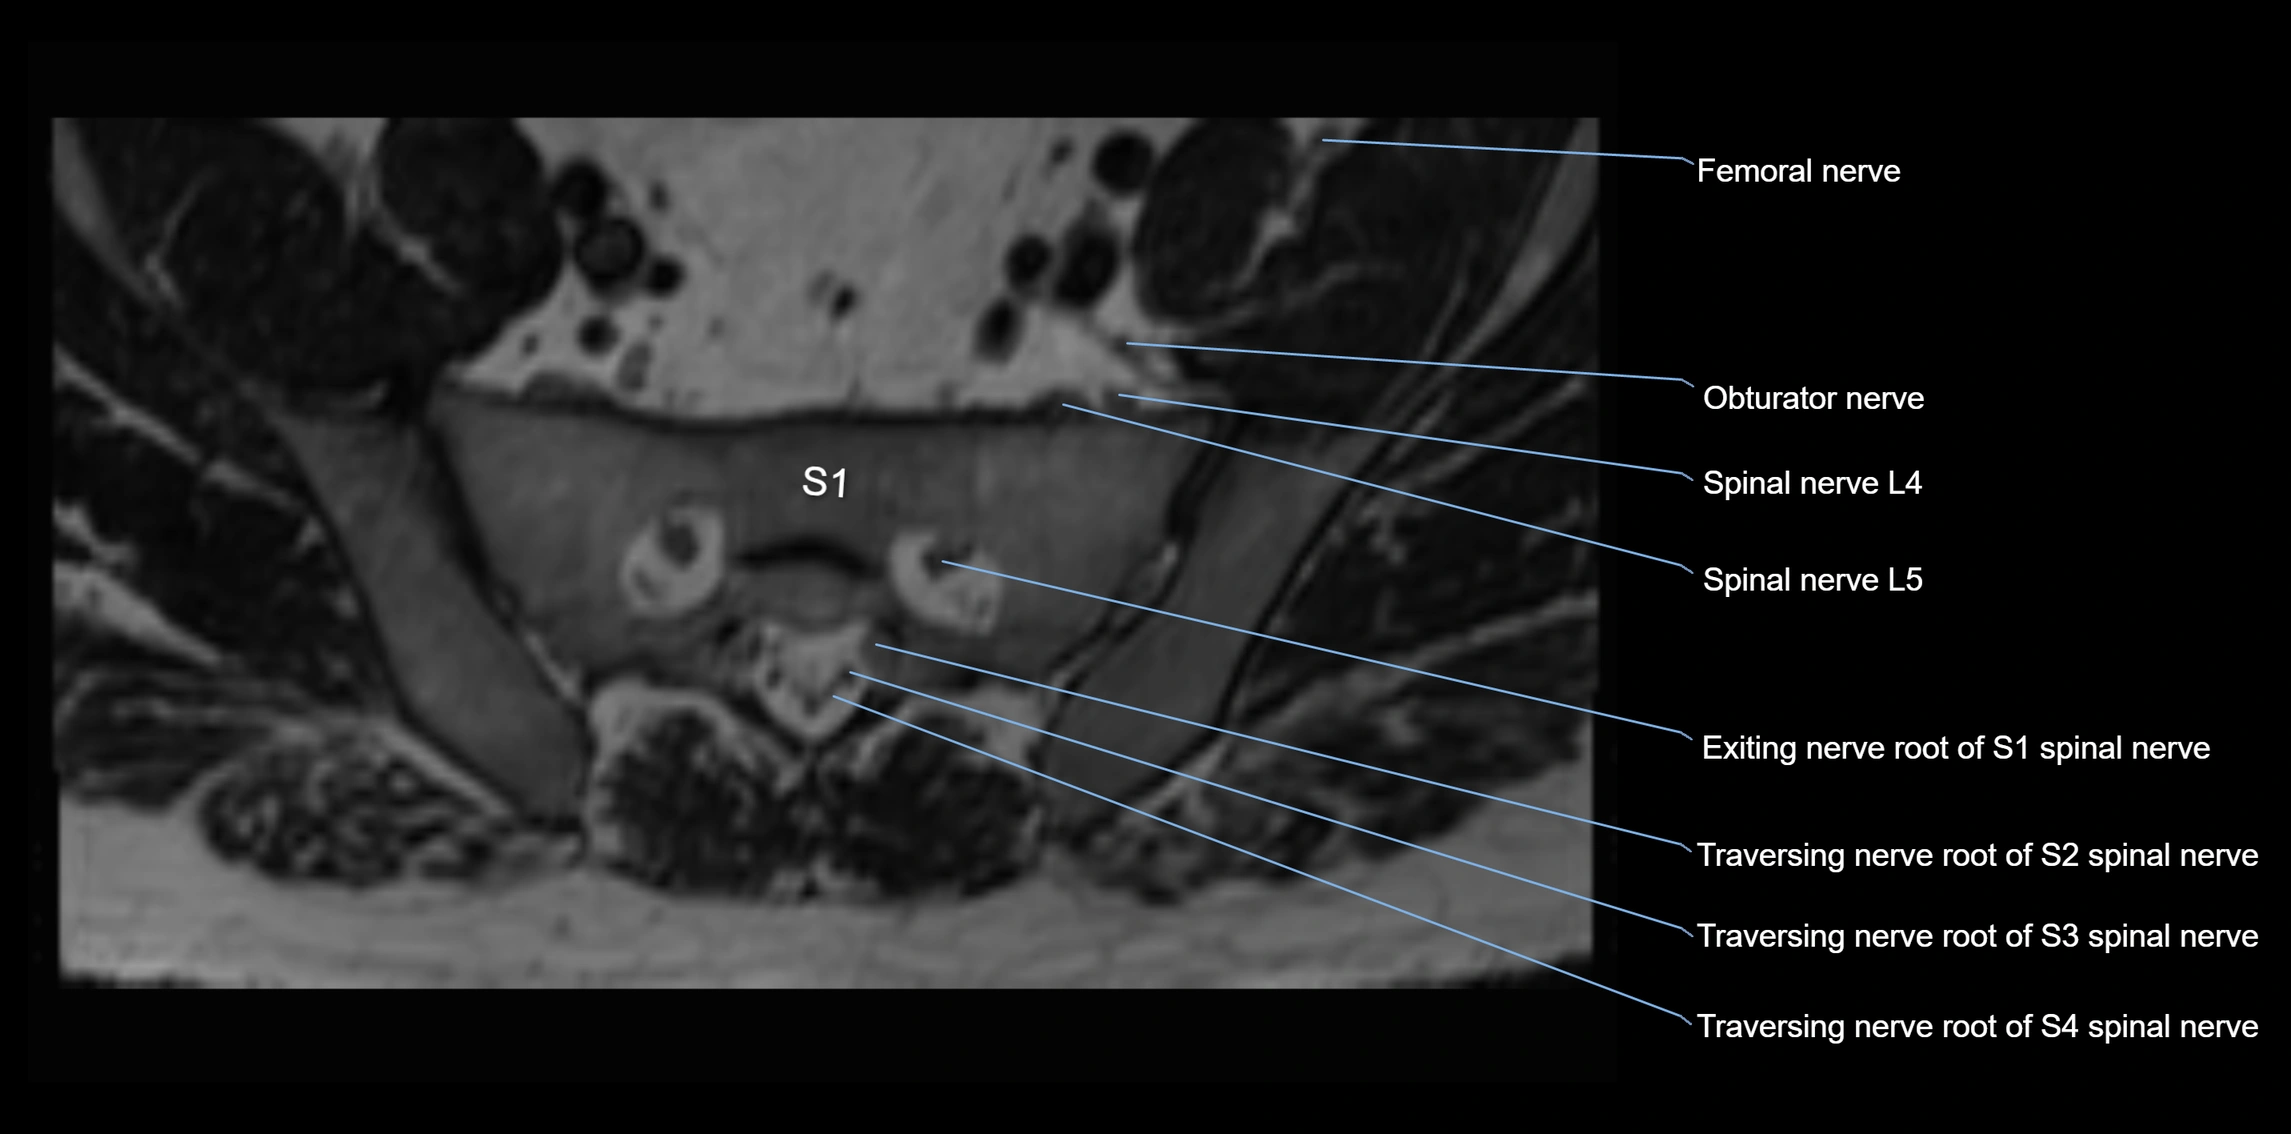

MRI image

image